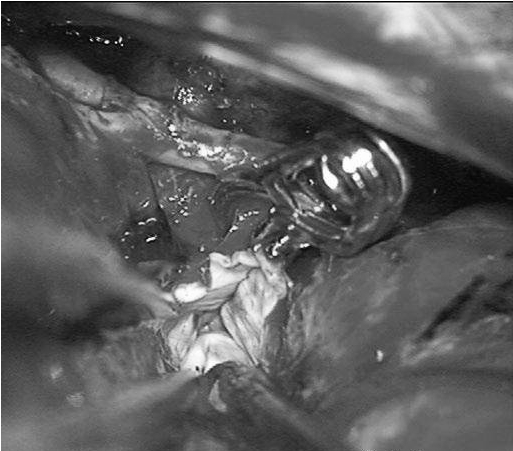

他紧急行半侧颅骨切除术,随后血管造影显示右侧动脉瘤,AVM由双侧PcaA供血,引流向前MedFrV和SplenV【左侧ICA像,(a)前后位(b)侧位】(c)首先通过双侧开颅并排夹闭动脉瘤(鼻朝右,中线呈水平,重力牵开右侧额叶),然后切开动脉瘤使之缩小。

(a)侧位(b)前后位].(c)他取侧卧位,右侧朝下,鼻朝下,中线取水平位以便靠重力牵拉右侧枕叶。窦汇开颅,显露SSS、TrvS、枕较、后纵裂和镰幕交界处。SplenA沿胼胝体压部上升,顺着它可达AVM(续)。